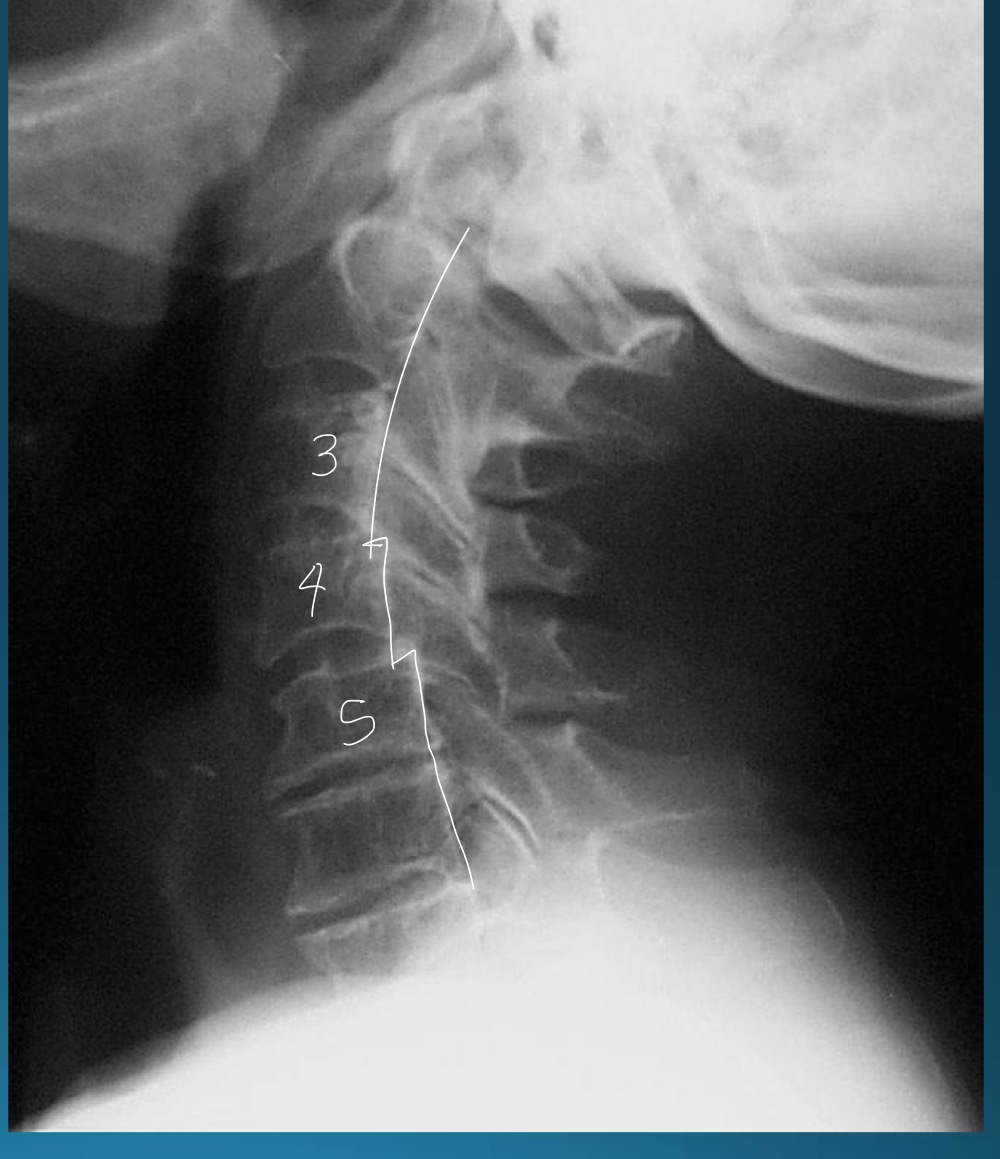

what are the findings in this image?

uncovertebral joint arthrosis

what do you call the radiographic feature commonly seen in uncovertebral joint arthrosis

pseudofracture